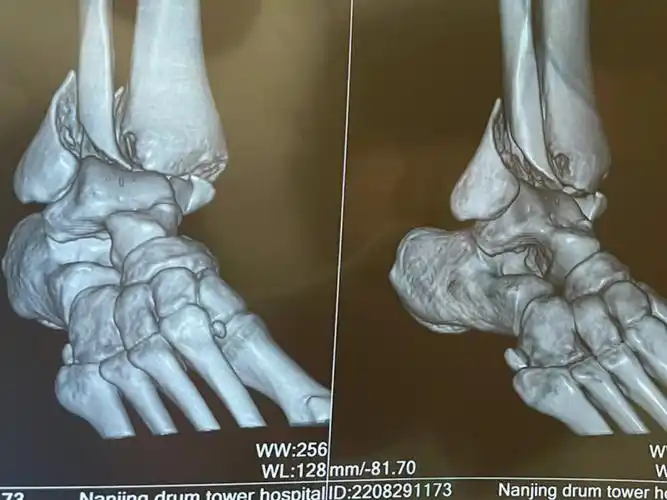

三踝骨折日记术前拍片